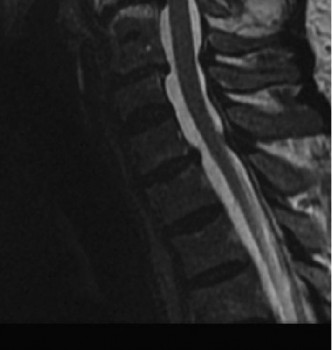

CASE 1 A 63-year-old male sustained a hyperextension injury to his neck while diving into a pool. Upon presentation, he reports decreased sensation in his hands and decreased strength in his arms and wrists, but no lower extremity complaints. On motor examination, he has 5/5 strength in his deltoids and elbow flexors and 4/5 strength in the elbow extensors, wrist extensors, and finger flexors. Lower extremity motor examination is normal. Sensation is decreased to light touch in both hands. Otherwise his sensation is preserved. Images of his cervical spine are shown in Figures 1–1 to 1–3.

Figure 1–3

The correct answer is (B). The clinical scenario describes a patient with central cord syndrome (CCS). CCS continues to be the most common incomplete spinal cord injury accounting for 15.7% to 25% of all spinal cord injuries. The characteristic presentation is an extension moment injury in a previously spondylotic and stenotic spine. Figures 1–1 to 1–3 demonstrate a spondylotic spine with central narrowing and CSF effacement that is worst at the C3–4 level. Bleeding, edema, and/or Wallerian degeneration lead to damage of the lateral corticospinal tract which is the main descending motor tract in the spinal cord. The more central anatomic position of the homunculus to the upper extremities places them at greater risk than those to the lower extremities. As such, injury to the lateral corticospinal tract is characterized by upper more than lower extremity involvement and motor deficits being more pronounced than sensory deficits.